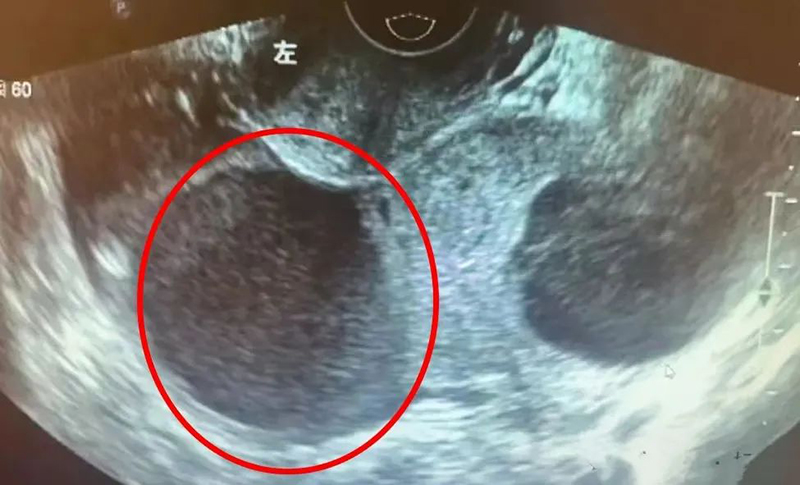

急診科快速啟動(dòng)急癥響應(yīng):查體發(fā)現(xiàn)患者腹部壓痛明顯,B超提示“盆腔內(nèi)探及60×45mm多個(gè)混合回聲團(tuán)塊,伴大量游離液體”——這是腹腔內(nèi)出血的典型信號(hào)。婦產(chǎn)科醫(yī)生第一時(shí)間趕來(lái),結(jié)合病史與影像學(xué)結(jié)果,初步判斷“腹腔內(nèi)出血,不排除卵巢囊腫破裂”,立即開(kāi)啟婦產(chǎn)科急癥綠色通道,一場(chǎng)與時(shí)間賽跑的救治就此展開(kāi)。

無(wú)影燈下,緊張感拉滿(mǎn),腹腔鏡探查結(jié)果印證了判斷:患者左側(cè)卵巢巧克力囊腫破裂,盆腔內(nèi)已積聚約200ml積血,卵巢破口處仍有活動(dòng)性出血。專(zhuān)家團(tuán)隊(duì)快速清理積血、囊腫的同時(shí),著重保留健康卵巢組織。劉主任表示,保護(hù)年輕患者的生育功能,是診療過(guò)程中必須優(yōu)先考慮的重點(diǎn)。2小時(shí)后,手術(shù)順利結(jié)束,患者血壓、心率等指標(biāo)恢復(fù)正常,安全返回病房。